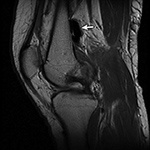

(B) Sagittal proton-density-weighted image of the knee shows blooming dark signal (arrow) secondary to intra-articular gas following traumatic arthrotomy. |